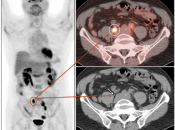

Colorectal Cancer

Recurrence & Restaging: (Most common indication)

- Rising tumor markers & negative (or indeterminate) CT scan.

- Restaging known recurrence, especially if surgery is contemplated.

- Distinguishing recurrence from post-therapeutic inflammation/scarring.